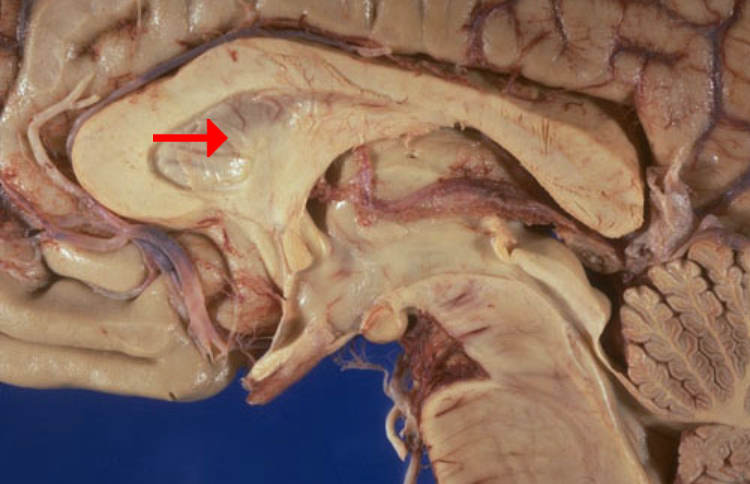

Label this brain part

Mammillary body